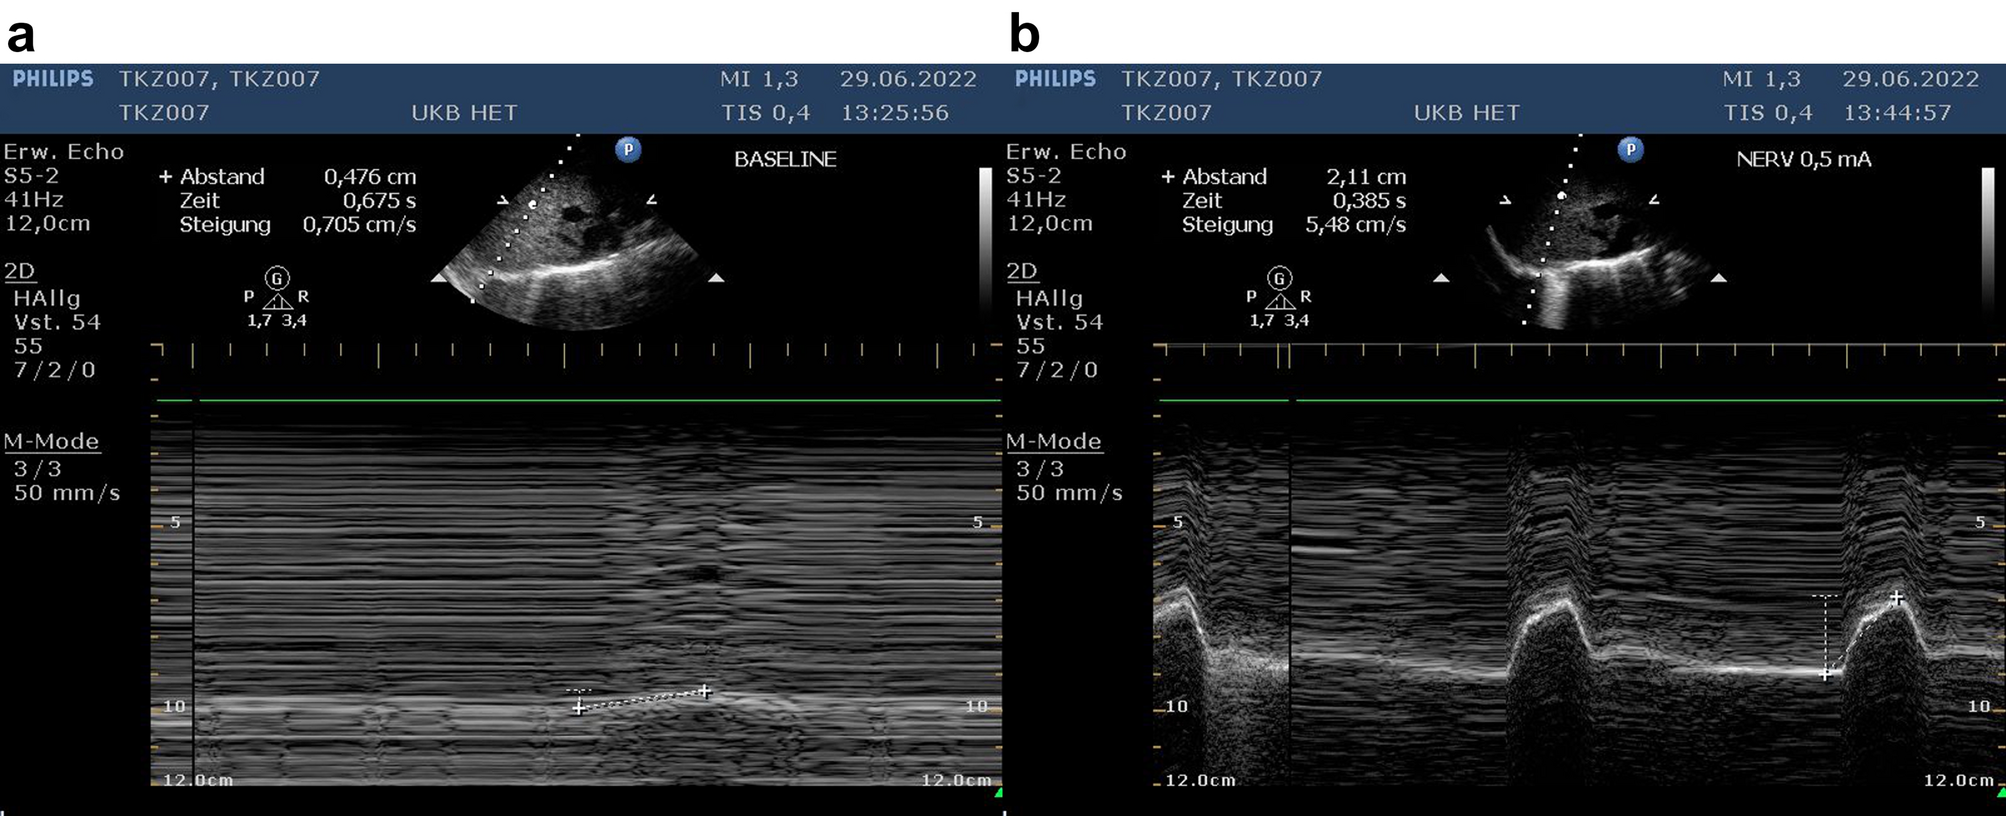

Figure 8

Ultrasound examination of the externally stimulated right phrenic nerve. (a) Minimal diaphragmatic excursion without stimulation during the inspiratory cycle of the respirator. (b) Regular diaphragmatic excursion following external stimulation of the nerve with a stimulus of 0.5Â mA.